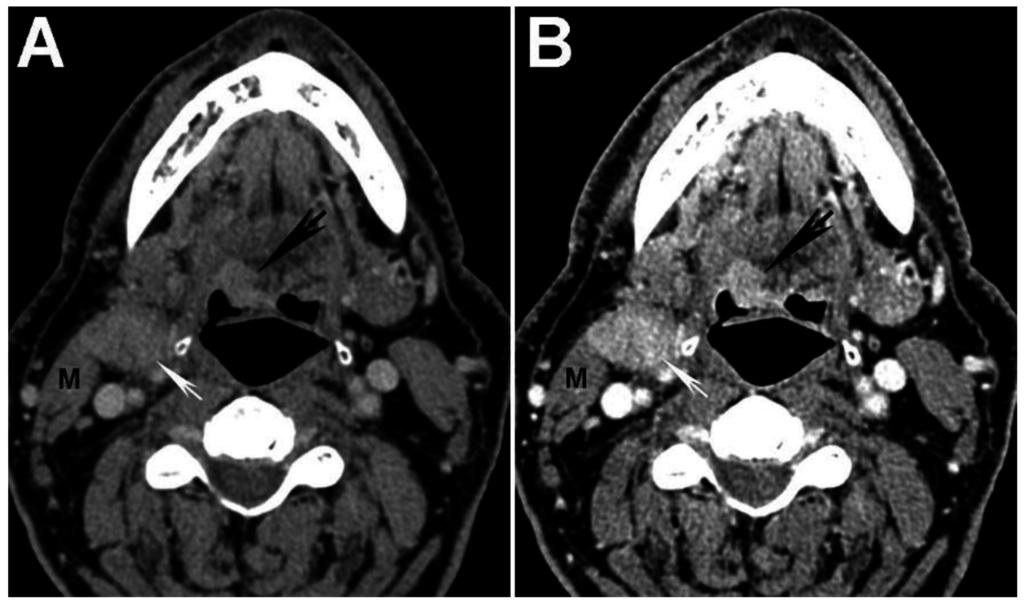

Figure 2. Increased tumor attenuation on 40 keV virtual monochromatic images (VMIs). (A) 70 keV single energy equivalent CT image of a right base of tongue tumor (large black arrow) and pathologic right level IIA lymph node (small white arrow) is shown. Note the similar density of both lesions compared to the normal right sternocleidomastoid muscle (M); (B) On the 40 keV image displayed using the same window-level settings, note the higher lesion density as well as higher relative contrast compared to muscle (M). Also note the increased image noise on the 40 keV VMI (B) compared to 70 keV VMI (A).